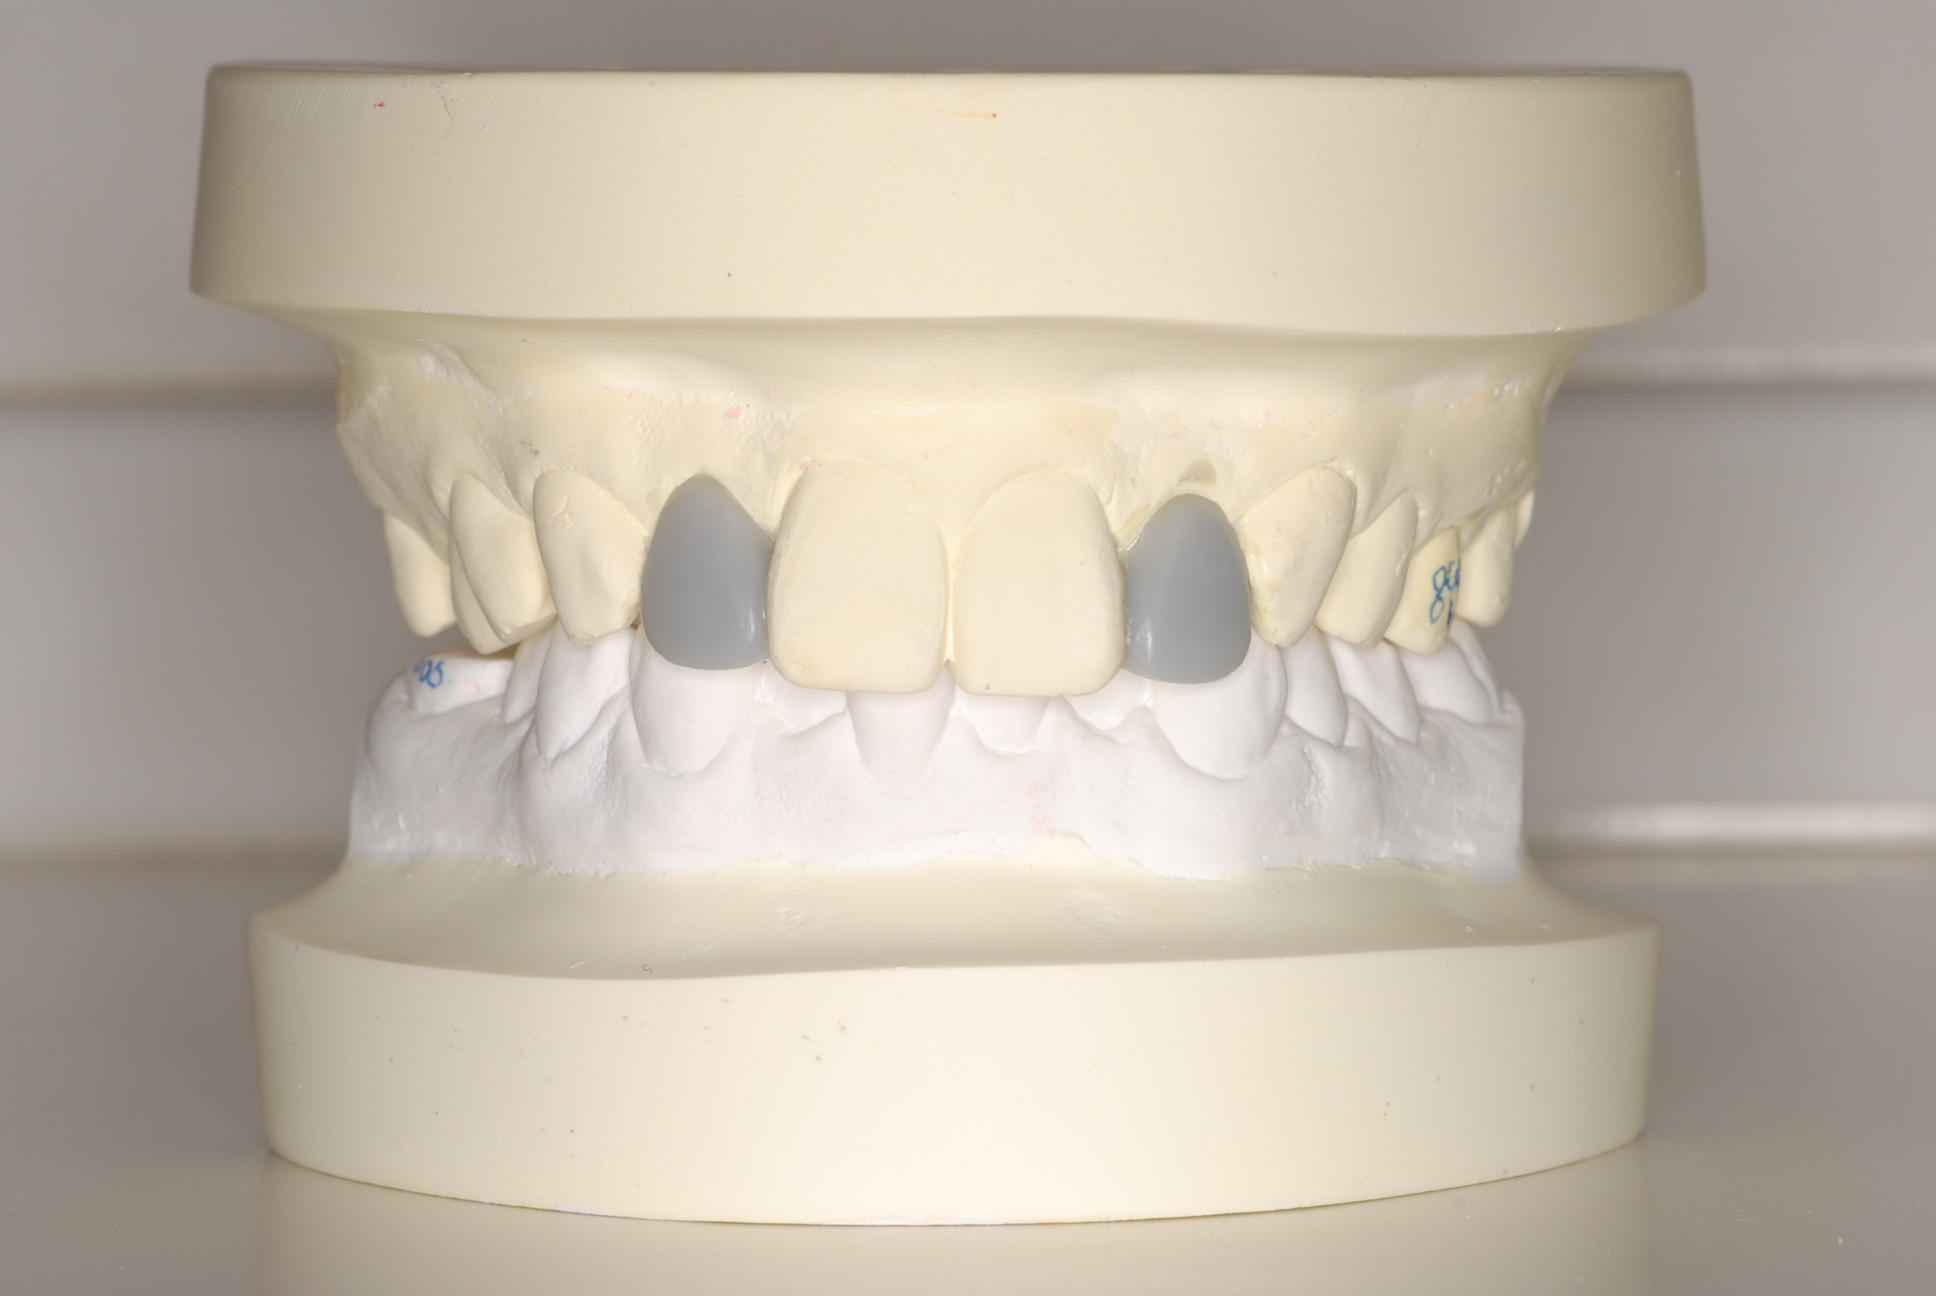

セットアップを作製。この時点でも患者さんと話し合い、TEK(仮歯)を作り、

患者さんが納得いく形を決めました。

セットアップ